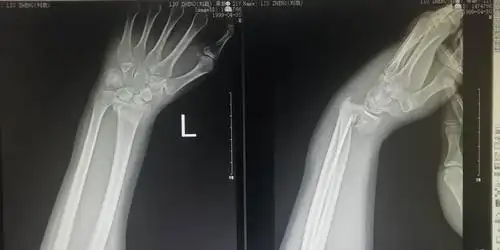

桡骨远端骨折史密斯

smith骨折 闭合复位小夹板治疗

难得一见的桡骨远端骨折 smith骨折 [病例帖]

smith骨折手法复位石膏固定